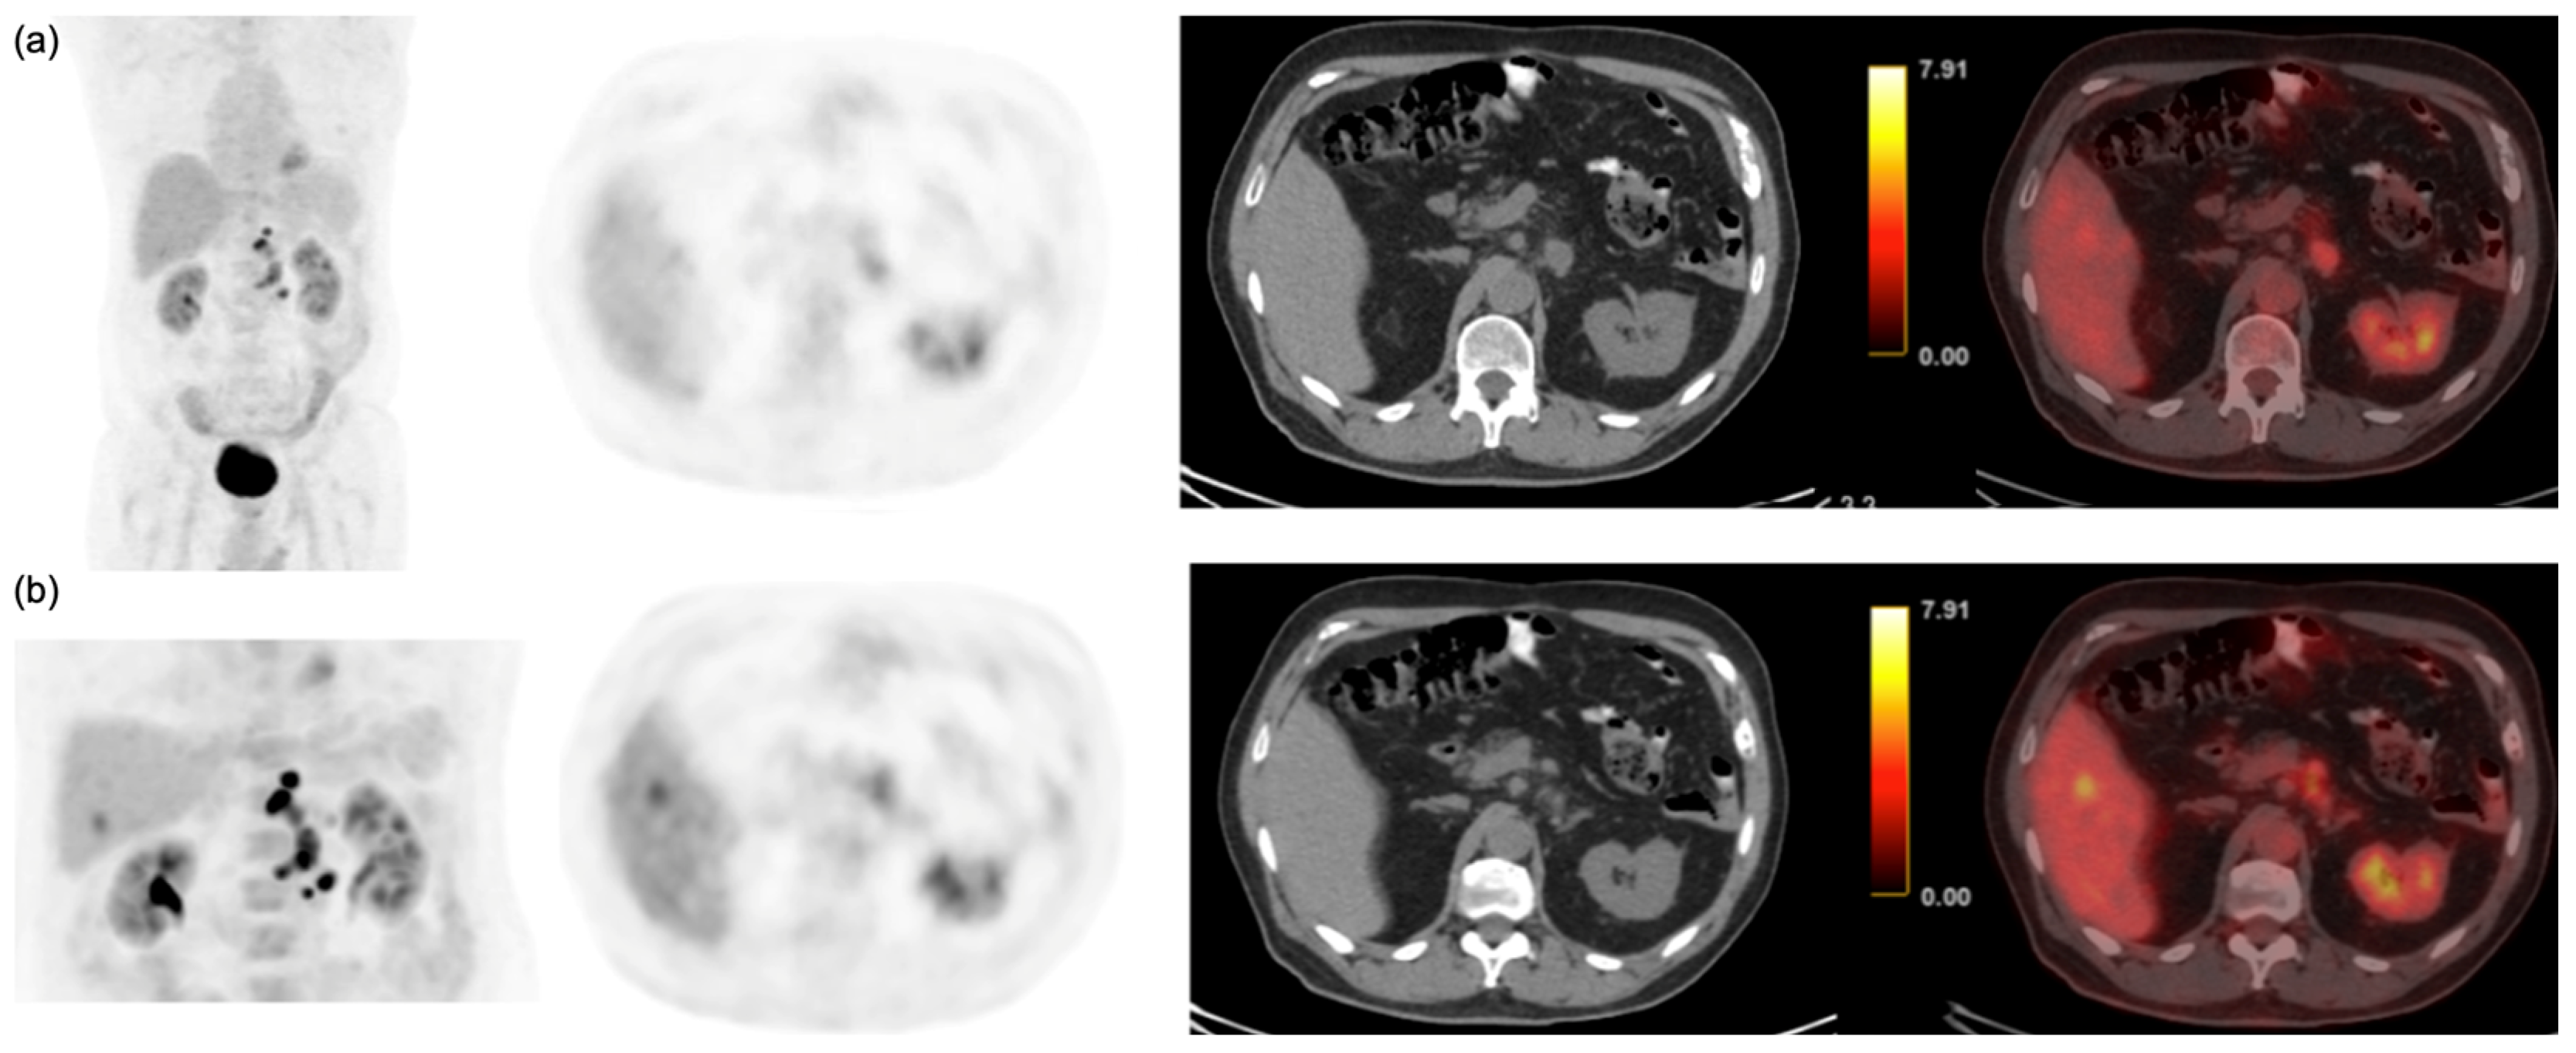

3.3. Semi-Quantitative and Per-Lesion Analysis

4. Discussion